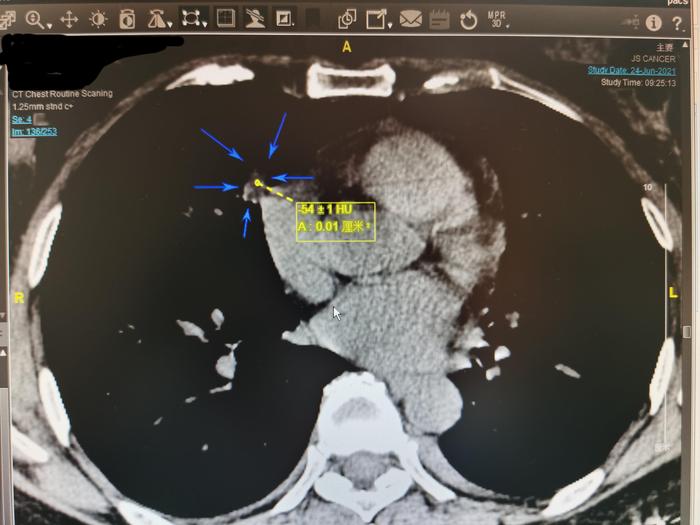

再看了几个薄层CT,上图,我用5个箭头指示这个右中肺实性结节,在薄层CT136层面,此结节的5条边都比较直。边缘笔直是良性结节的特点。

我仔细测量薄层136层面其中一小块发暗的区域,CT值为-54,说明局部有脂肪密度,此实性结节内部有脂肪成分。有脂肪成分的实性肺结节一般是良性肺结节。